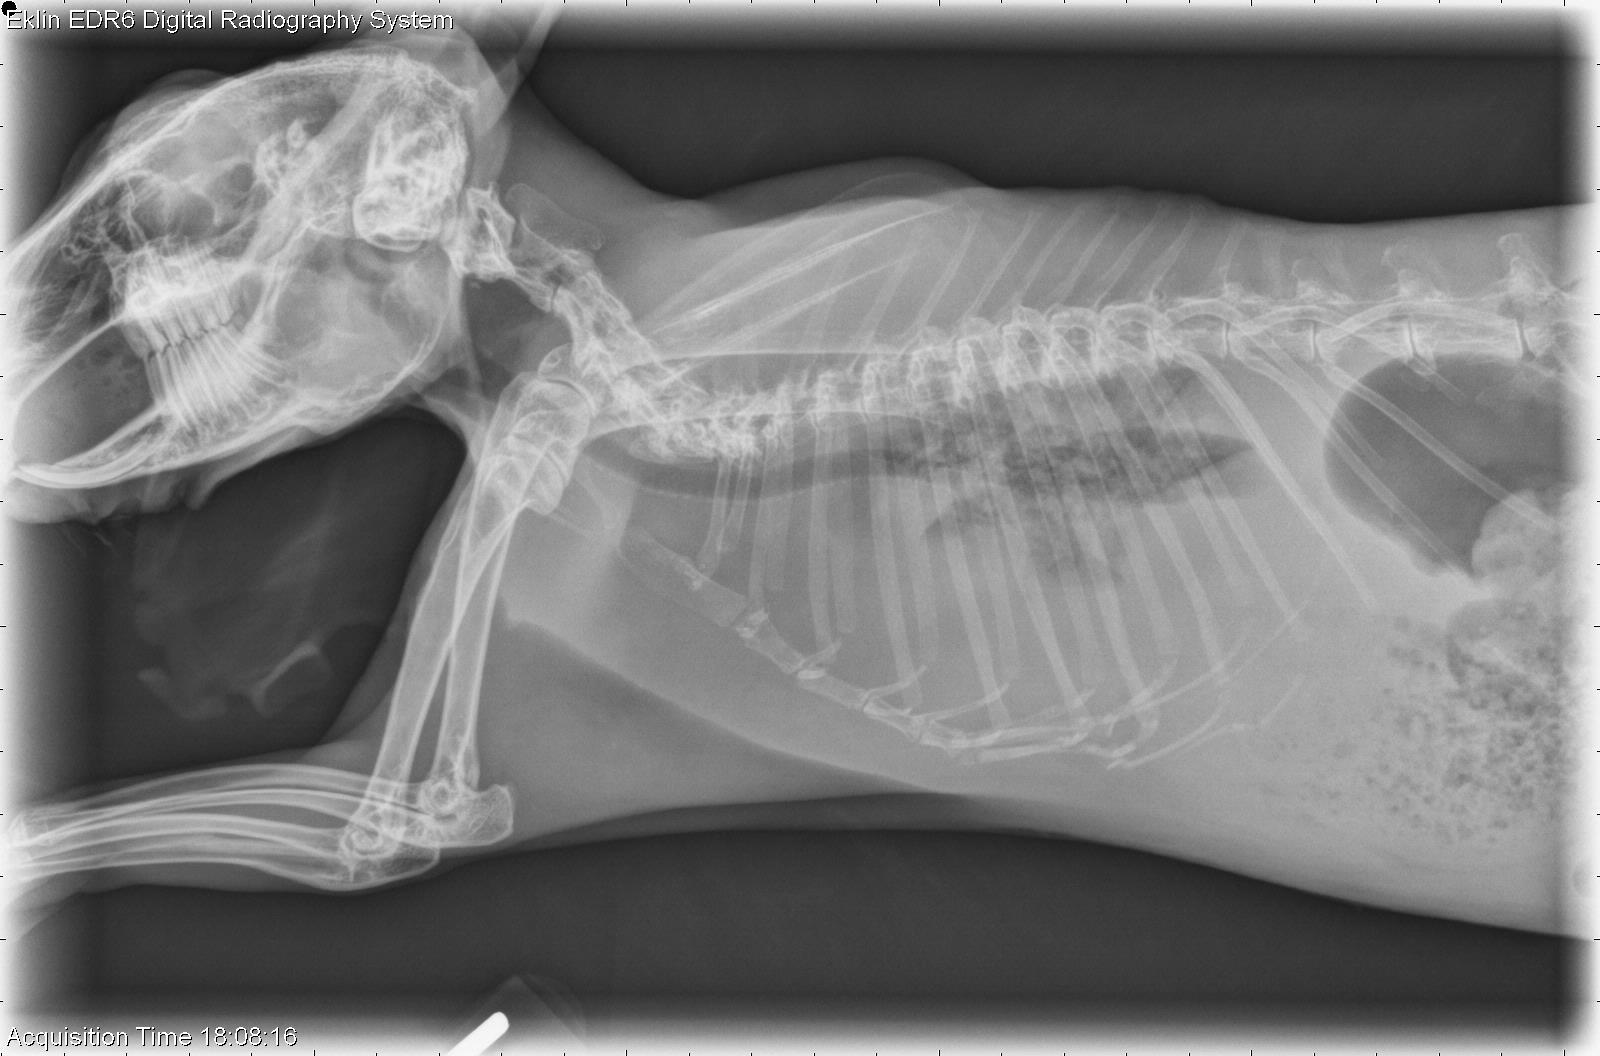

Heart Disease in Companion Rabbits: Causes, Diagnosis, and Treatment

As companion rabbits live longer, the diagnosis of cardiac disease has become more common, influenced by factors such as age, genetics, concurrent diseases, and... Read more.